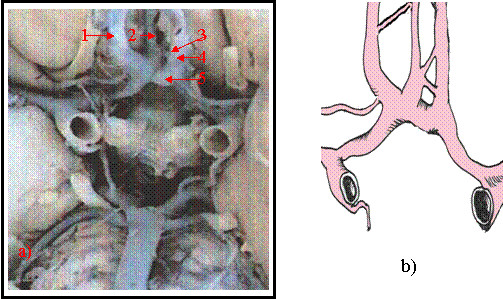

Cazul 4 [figura 9.4 a) si b) ]

La acast caz artera carotida interna stanga dupa un traiect de 7mm de la emergenta arterei comunicante posterioare se bifurca in artera cerebrala mijlocie cu orientare spre lateral ce se angajeaza in scizura lui Sylvius si segmentul scurt A-1 al cerebralei anterioare stangi. Segmentul A-1 la randul sau se bifurca in artera cerebrala anterioara stanga segmentul A-2 si o artera comunicanta anterioara lunga de calibru larg ce se continua cu segmentul A-2 al arterei cerebrale anterioare din dreapta. De pe flancul antero-superior al comunicantei anterioare se detaseaza o artera cerebrala anterioara mediana care se va anastomoza printr-o artera comunicanta cu segmentul A-2 al cerebralei anterioare stangi, iar printr-o alta comunicanta cu segmentul A-2 al cerebralei anterioare drepte, realizand o fereastra vasculara. Segmentul A-1 al cerebralei anterioare din dreapta la fel cu artera comunicanta posterioara dreapta sunt lungi si filiforme. Debitul sanguin al carotidei interne din partea dreapta se repartizeaza predominent in artera cerebrala

Figura 9.4 a) vasele poligonului lui Willis disecate pe encefal b) prezentare schematica

1-.artera carotida interna stanga. 2. segmentul A-2 al cerebralei anterioare stangi si a doua comunicanta anterioara ce formeaza butoniera vasculara. 3 - artera cerebrala anterioara mediana. 4 - segmentul A-2 al cerebralei anterioare drepte. 5.- segmentul A-1 al cerebralei anterioare drepte. 6 - artera comunicanta anterioara. 7 - artera comunicanta posterioara.

mijlocie in timp ce segmentele A-2 si P-2 din partea dreapta sunt alimentate predominent din artera carotida interna stanga, respectiv trunchiul arterial bazilar.